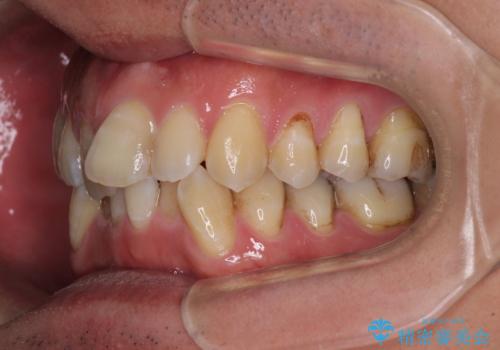

- 前歯のデコボコを気にして来院された患者様です。

下顎前歯のデコボコが特に強く、治療を早く終えることを考えるとワイヤー装置がお勧めですが、ワイヤー装置の異物感は避けたいのでインビザラインを希望されていました。

インビザラインで治療を行うか、ワイヤーで治療を行うかずっと悩んでいらっしゃいましたが、早く終わらせることを優先してワイヤー装置にて治療を行うこととしました。

下顎にワイヤー装置を装着し、暫くしたところでやはりインビザラインにて矯正治療をしたいとのことで、インビザラインに切り替えました。

短い期間でしたがワイヤー装置を使用したことでデコボコが解消されたため、インビザラインの比較的短い期間で矯正治療を行うことができました。